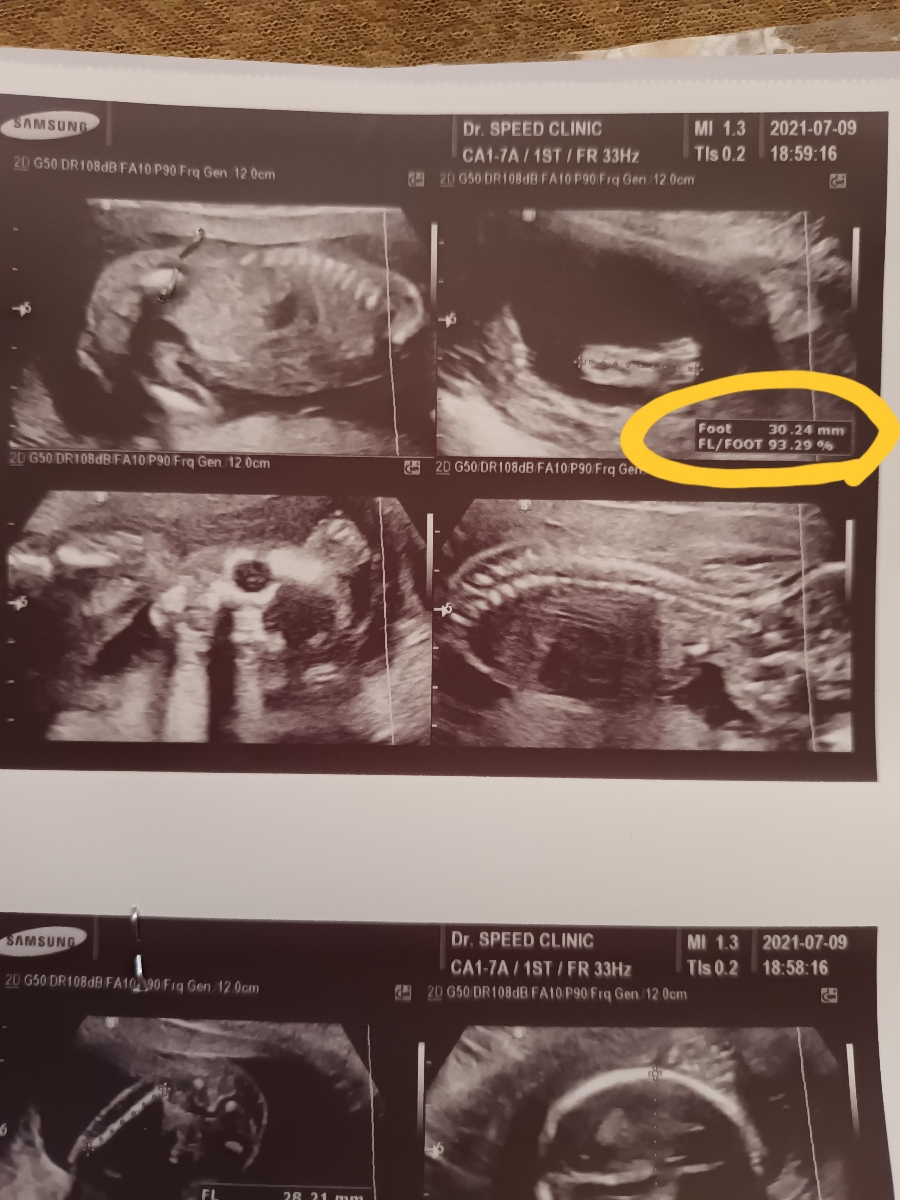

این قسمت ک علامت زدم انگار یکم زیاده. استخوان ران Fl/foot =144% (85-111%)

البته اینجا FL رو زده ۲۸mm

الان تماس گرفتم مرکز سونو گفتن ک این نسبت ران به کف پا هست. و احتمالا اشتباه تایپی شده!!!!

چون رو عکس درصد رو زده ۹۳.۲۹٪